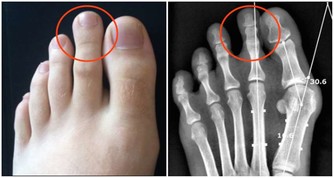

另 外,蔡立泰醫師也表示,扁桃腺結石通常看起來像白色或微黃色的小石頭,有時候吐出來時,可以把這些小石頭壓碎,並出現臭臭的味道。扁桃腺結石目前 大多認為是由食物的殘渣及壞菌卡在扁桃腺表面的隱窩中所形成。有些人會感覺到喉嚨卡卡的感覺,嚴重的患者更可能出現頭痛、咽喉疼痛、吞嚥困難、耳朵痛癢、 甚至嘔吐等情形。也因為這些細菌和食物的殘渣以及部分壞死組織的鈣化,所以可能在講話時散發出一些腐爛的臭味,也就是我們所謂的口臭。

才發現原來這是扁桃腺結石,

他耐心的用畫圖方式告訴我結石藏在扁桃腺的隱窩,不易清除,